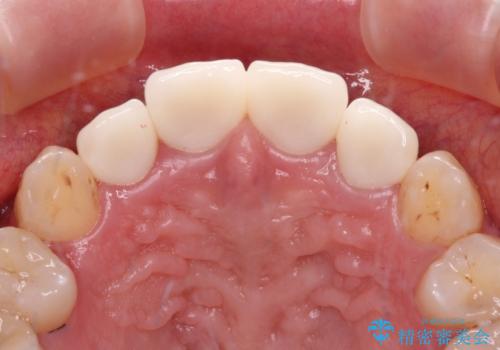

上顎前歯や下顎大臼歯に根管治療の必要な歯がいくつかあるため、矯正治療と並行して根管治療を行い、その後オールセラミッククラウンにて補綴治療を行うこととしました。

開咬の改善には舌突出癖を改善するためのトレーニングが必要ですが、しっかりと行っていただき、想定よりも早い期間で治療を終えることができました。